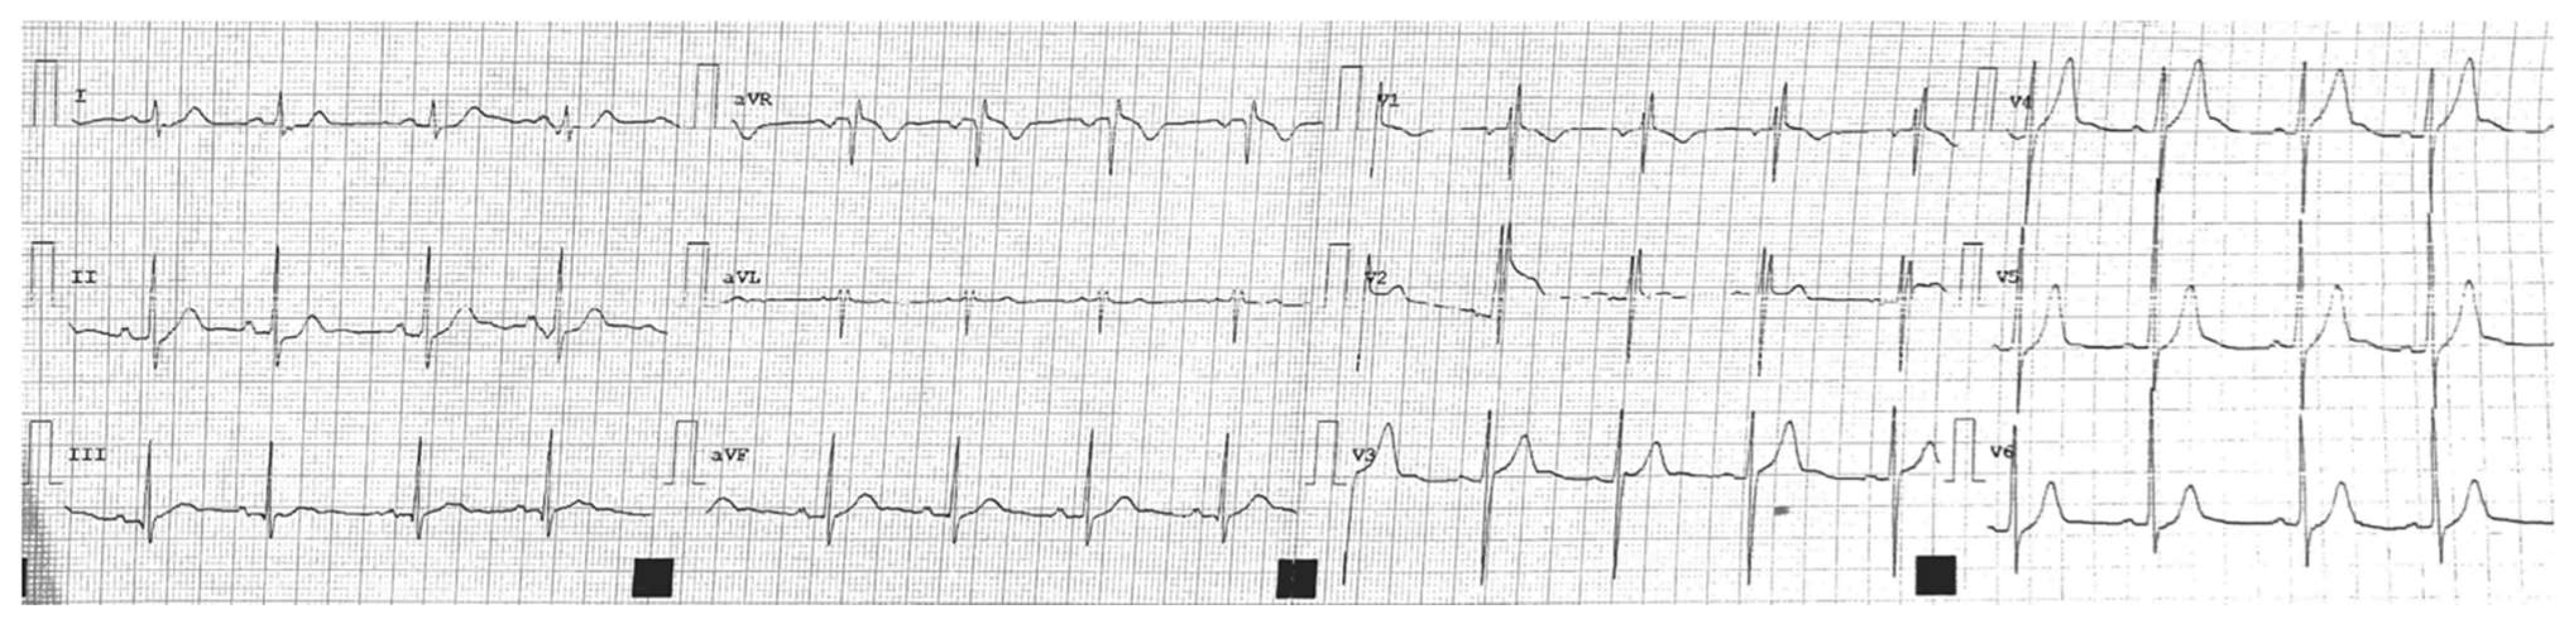

2. Case 1